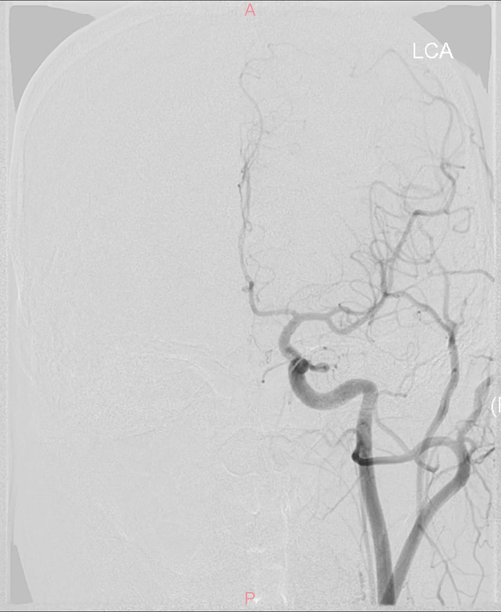

造影显示左小脑动静脉畸形,由左侧小脑上动脉中央支和外侧支、左侧小脑前下动脉中央支和外侧支、左侧小脑动脉后下动脉软膜支供血,经半球上浅静脉引流入直窦,小脑上动脉中央支远端可见巢外动脉瘤,动静脉畸形前界可见巢内动脉瘤

复查造影示动静脉畸形部分栓塞,前界及巢内、巢外动脉瘤不显影,残留供血来自于左侧小脑前下动脉软膜吻合支

左椎动脉正侧位复查造影,未见动静脉畸形显影